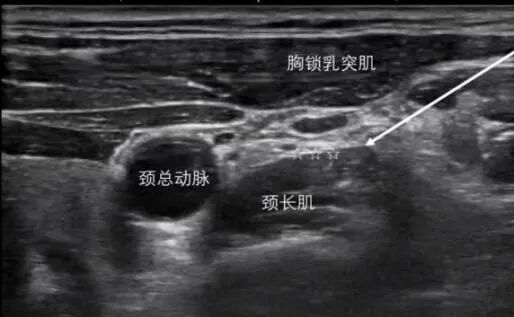

根據每位患者的具體情況,采用多樣化的治療方法,包括睡眠監(jiān)測、人工壓力滴定、認知行為療法、星狀神經節(jié)阻滯、中醫(yī)治療等,幫助患者擺脫藥物依賴,建立無藥睡眠。

星狀神經節(jié)阻滯 行為認知療法